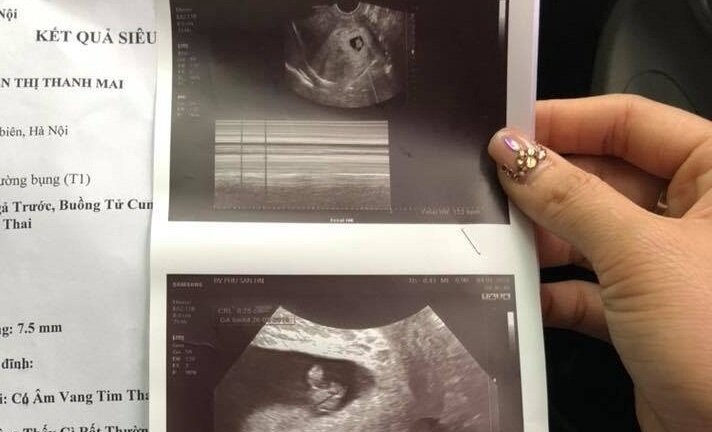

Bác sĩ chẩn đoán nhầm khuyên thai phụ bỏ thai, trong khi bệnh nhân chỉ bị dọa sảy tại Bệnh viện Đa khoa Đức Giang (Hà Nội) bị điều chuyển công tác xuống phòng Kế hoạch Tổng hợp.